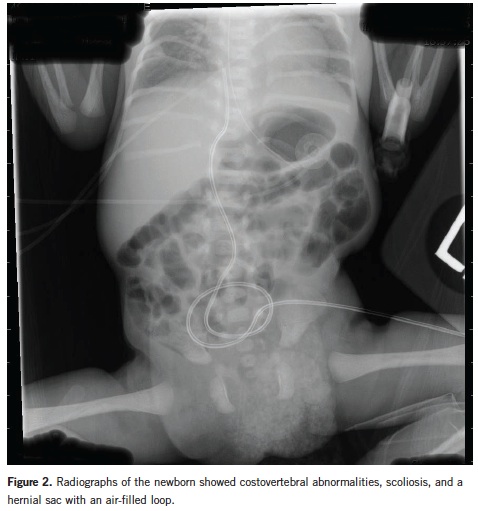

Plain chest and abdominal radiographs showed air-filled loops of bowel within the left lumbar region, scoliosis, and vertebral and costal abnormalities (Figure 2). The 6th through 12th ribs on the right and the 3rd through 9th ribs on the left were hypoplastic, and one rib was missing on the right. Thoracic vertebral bodies 8 through 10 also were hypoplastic, and mild lumbar scoliosis was noted.